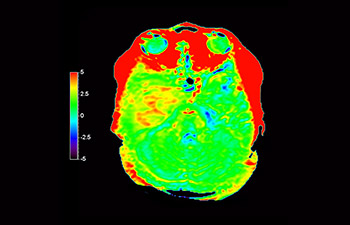

Brain astrocytoma, post-radiotherapy

with 3D APT